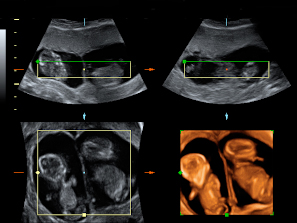

Vemos tres planos de un embarazo de trillizos en ecografía 2D en diferentes cortes de imagen. Lo que vemos en 3D es lo que los ecografistas conocen como "un queso", es decir el embarazo visto en tres dimensiones desde una perspectiva determinada. Lo que realmente esconde ese peculiar queso es un embarazo de trillizos: un feto independiente, separado de sus hermanos por una membrana.

Imágenes de trillizos de 13 semanas en ecografía 2D

Los gemelos se desarrollan en dos bolsas diferentes. En otro corte de la imagen, se ve un embrión independiente separado por una membrana de los otros dos hermanos, que se sitúan en bolsas independientes.